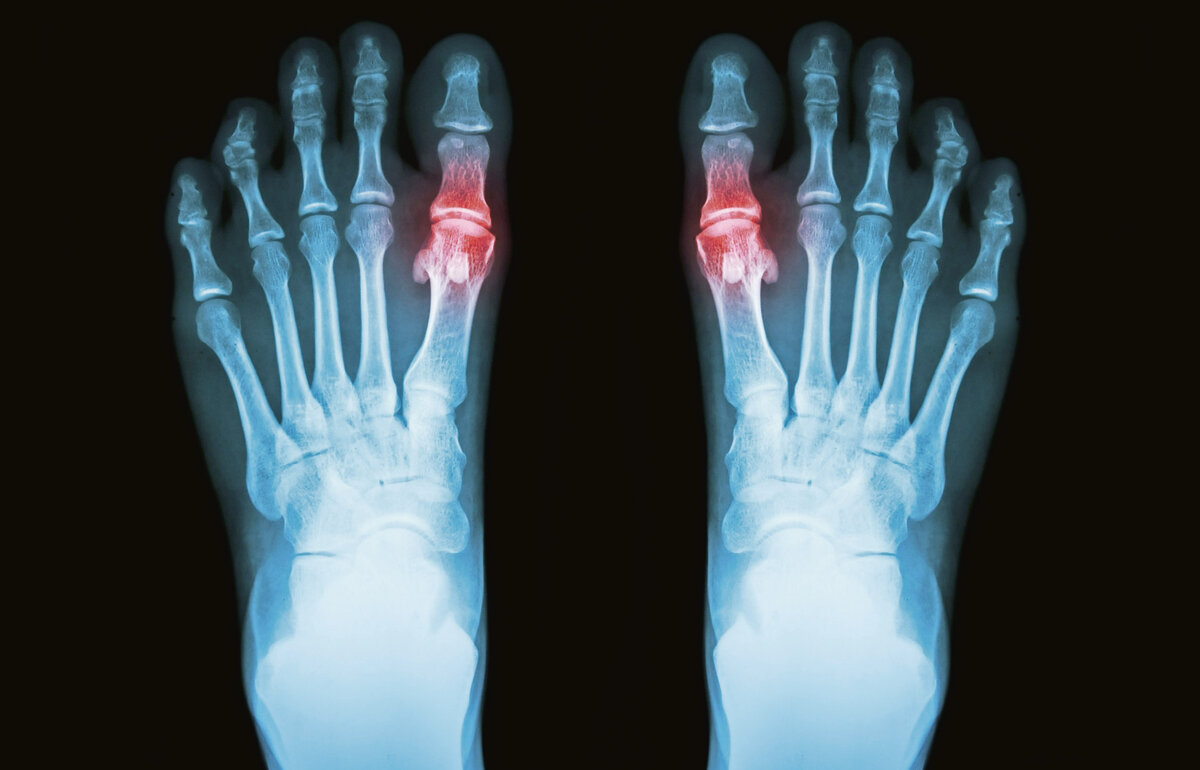

Подагрический артрит возникает при нарушении обмена мочевой кислоты: повышается её содержание в крови с последующим накапливании в мягких тканях. Это происходит оттого, что почки не справляются с химической нагрузкой  из-за неправильного питания или злоупотребления алкоголем. Проблема проявляется в виде постоянных обострений артрита: болят, как правило, мелкие суставы стопы, реже  –  голеностопный и коленный суставы, пальцы рук.

Сначала нарушается обмен мочевой кислоты, её содержание в крови увеличивается. Затем кристаллы мочевой кислоты оседают на поверхности сустава, возникает раздражение, а потом и повреждение сустава, которое сопровождается воспалением. Если не лечиться, сустав разрушается, в нём образуются полости, заполненные кристаллами мочевой кислоты, вокруг сустава появляются опухолевидные образования.

В 90% случаев первым подагра поражает большой палец одной из ног. Сначала возникает боль, и если в этот момент не начать лечение, то  болезнь начнёт перекидываться на другие мелкие суставы. При активном воспалении кожа над суставом краснеет, повышается температура. Боль усиливается при появлении под кожей вокруг сустава белых узелков мочевой кислоты, их видно даже невооружённым глазом. Хрящевая ткань постепенно разрушается, полости, заполненные мочевой кислотой, появляются даже в костях, примыкающих к суставу. Подкожные узелки и костные разрастания могут деформировать ногу до неузнаваемости. Если не лечиться, можно полностью потерять подвижность.